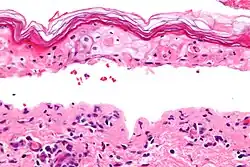

Micrograph of confluent epidermal necrosis. H&E stain.

In dermatology, erythema multiforme major is a form of rash with skin loss or epidermal detachment.